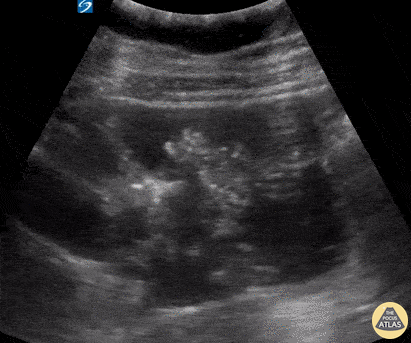

Bowel-GI - SBO with "To-and-Fro"

A 58-year-old female with multiple prior abdominal surgeries presented with a 2-day hx of abdominal pain and N/V. ROS also notable for anorexia and constipation. Abdominal POCUS seen here revealed dilated bowel loops with thickened and hyperechoic bowel walls. “To-and-fro” movements of the bowel contents are also appreciated. This occurs as a consequence of increased intestinal contents and peristalsis, otherwise known as dysfunctional peristalsis. All of the aforementioned are consistent with a diagnosis of SBO. When there is high clinical suspicion of SBO, POCUS can serve as an inexpensive and rapid adjunct for clinical evaluation, expediting time to disposition. Dr. Samantha Wong, @esayemDO EM Resident. Central Michigan University